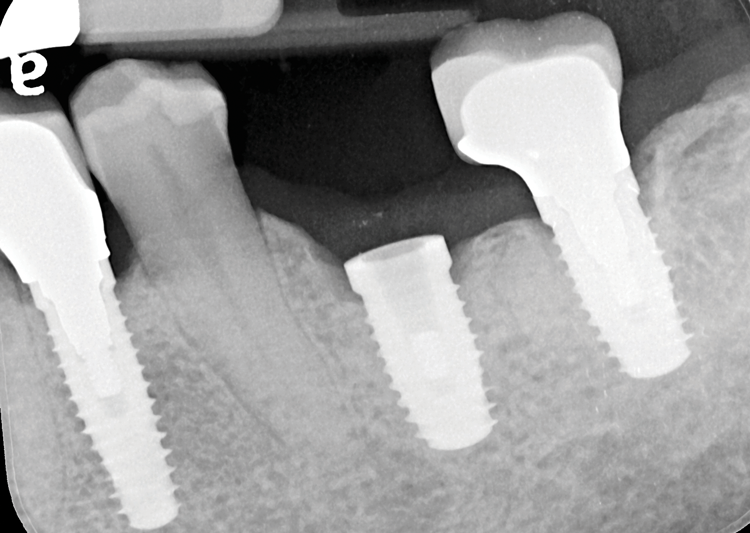

A 61-year-old male patient presented with the chief complaint of a missing implant-supported crown. The patient's dental history revealed a habit of grinding and clenching, and signs of wear were clinically evident during the examination. Because the implant restoration was placed 7 years prior at another practice, and the manufacturer and model were not immediately available, a universal protocol would be required to attempt the rescue. The patient reported that the crown had been dislodged for many weeks. As a result, the soft tissue had grown over the implant, completely covering it (Figure 2). A preoperative periapical radiograph was taken to help visualize the location and size of the remaining fragment (Figure 3). In addition, an intraoral camera would be used during the procedure to view the internal aspect of the fixture and aid in the retrieval process.